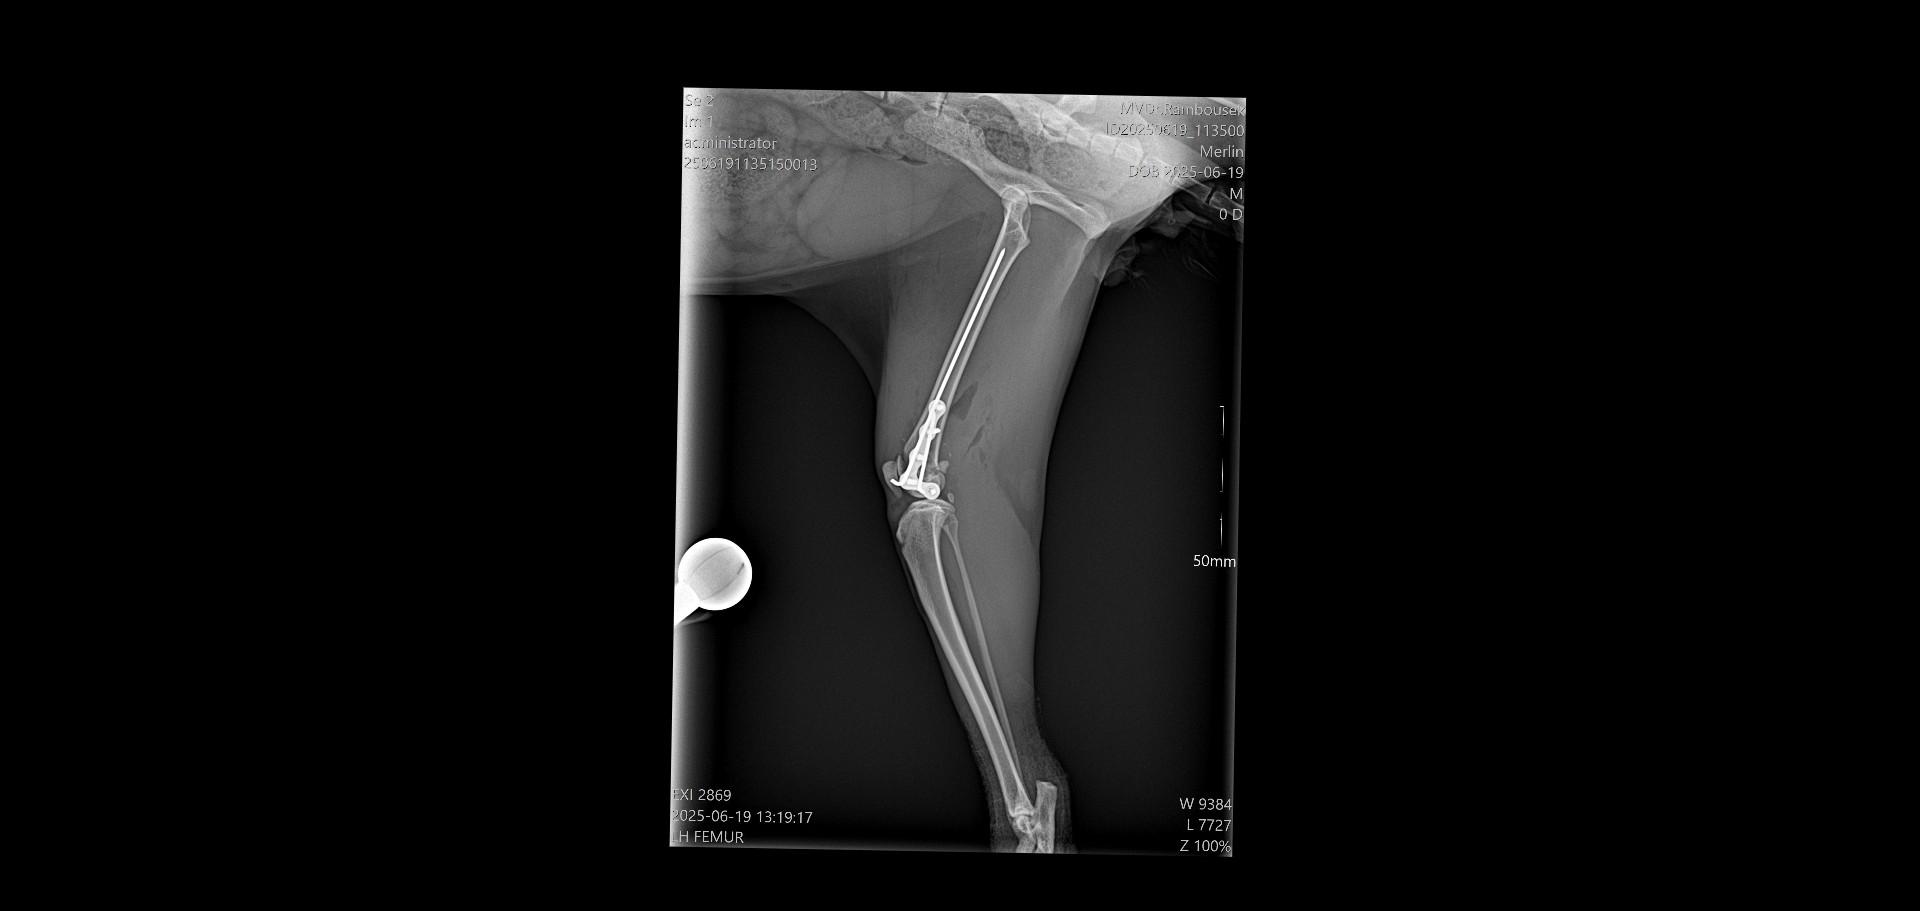

Dnes ráno měl  být Merlinek propuštěn do domácího léčení, bohužel jeho stav po narkóze neodpovídal běžnému stavu a musel ještě zůstat na klinice. Zítra budeme vědět víc a doufáme, že bude už v pořádku a pojede s námi domů, kde má vše připraveno na doléčení. Přikládáme snímky z rentgenu operované nožky. Děkujeme všem za podporu a pomoc s úhradu nákladů na operaci a hospitalizaci, které budou vysoké, bez vaší pomoci bychom to nezvládli.